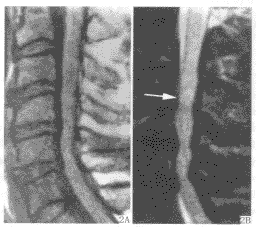

MRI表現三MRI表現

1.多發在長管骨的乾骺端,病灶呈圓形或橢圓形,其長軸與長骨縱軸一致。

2.病灶於T1WI上多呈低或中等均勻信號,T2WI呈明顯均勻高信號,若囊液內有出血或含膠樣物質則T1WI和T2WI上均呈高信號,少數呈多房改變時T2WI上可見低信號纖維間隔。

3.病灶周邊骨殼呈圓圈樣低信號,一般完整,邊緣清晰。局部骨皮質變薄,無骨膜反應。常伴發病理性骨折,表現為骨皮質斷裂,骨片陷落而插入病灶內,稱之為骨片陷落征(fallenfragmentsign),此征在T2WI上顯示較清晰即在高信號的囊液中見低信號的骨片線條影。

4.增強掃描:病灶不強化。